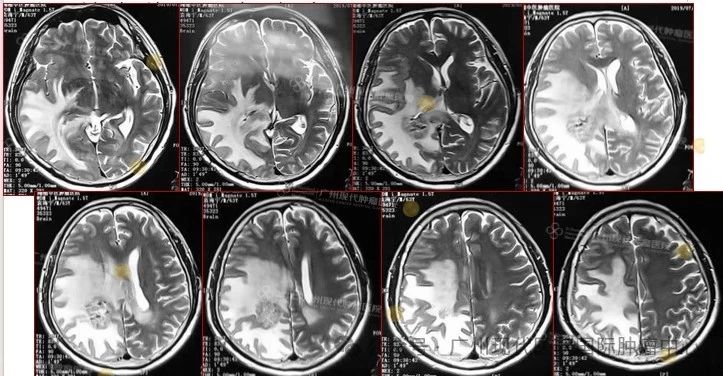

患者:63岁,男性

2013-11,体检发现肺部肿瘤,

2015-11,头颅MR检查提示颅内转移

2018-11,颅内肿瘤进展,无法接受后续治疗

2019-3,接受脑瘤粒子植入术

2019-7,颅内肿瘤基本消失,正常生活至今

2019年7月,颅内肿瘤已基本消失